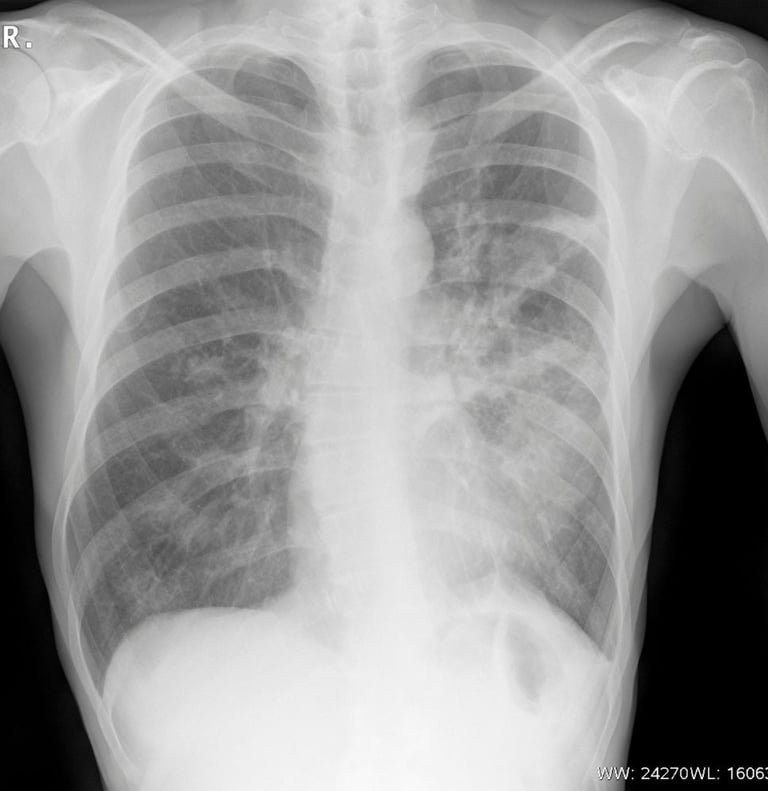

Dr. Memet Işık Notu: Skolyoz teşhisinde altın standart fiziksel muayene ve "Skolyoz Grafisi" adı verilen boydan boya çekilen röntgenlerdir. Bu sayede "Cobb Açısı" ölçülerek tedavi haritası çıkarılır.